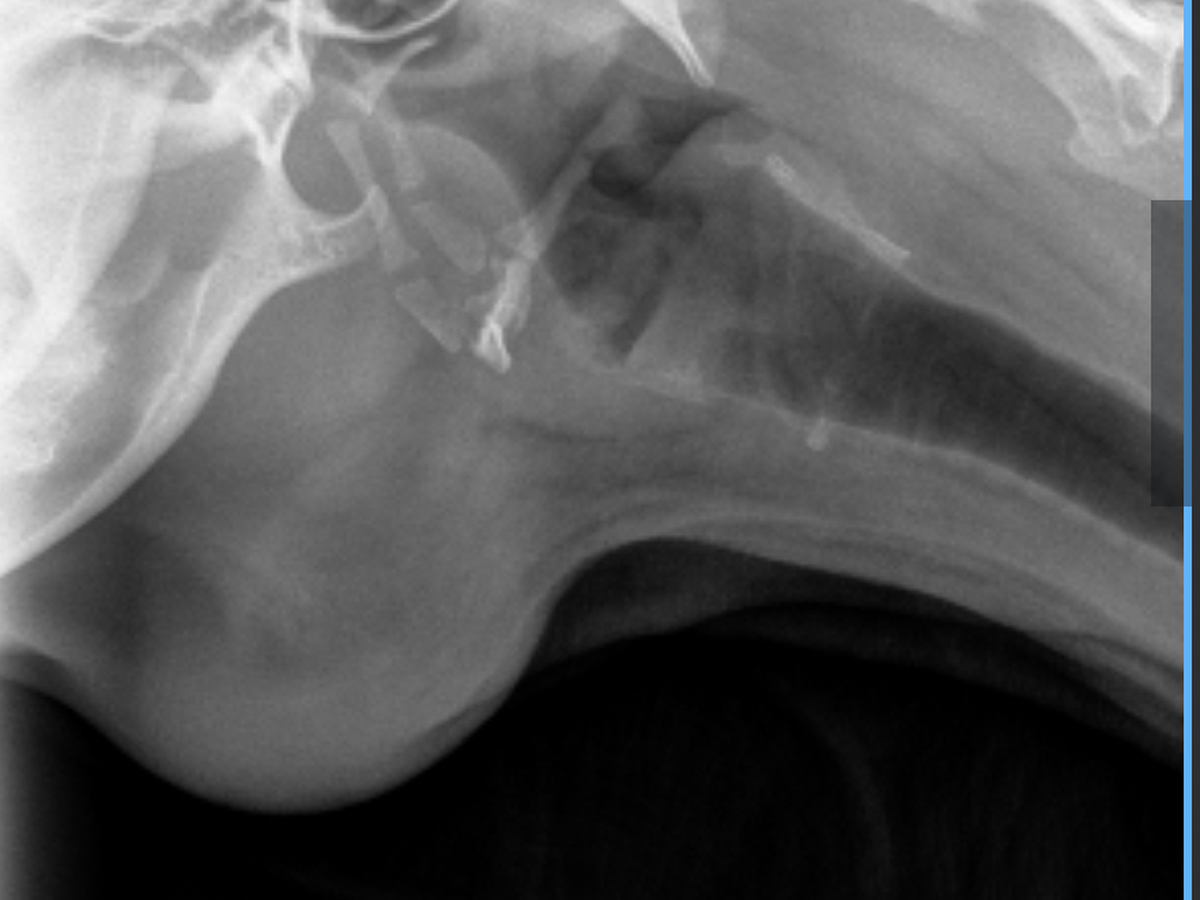

From the very beginning, Luna’s care team has worked tirelessly. She was sedated so her mouth could be explored, and started on antibiotics and pain medication. When the infection returned after her first round of treatment, her vet prescribed another course. As the abscess grew larger and harder, Luna underwent a fine needle aspiration and more advanced antibiotics. For a few days, it seemed like she was improving, but the infection came back stronger. At her latest appointment, Luna had x-rays and an ultrasound to rule out anything lodged in her throat. Thankfully, no foreign objects were found, but her vet felt surgery was too risky due to the size and location of the infection. That’s when we were referred to specialists, and now Luna must be seen as an emergency patient to get the care she needs.